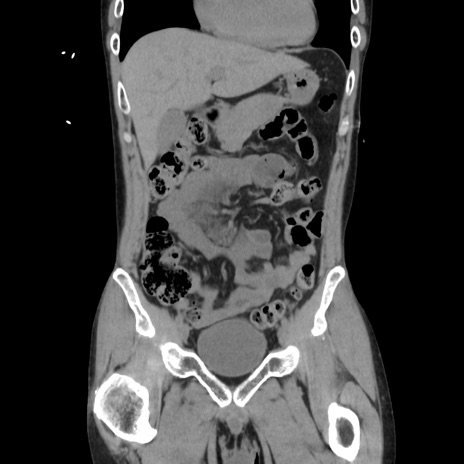

横断像